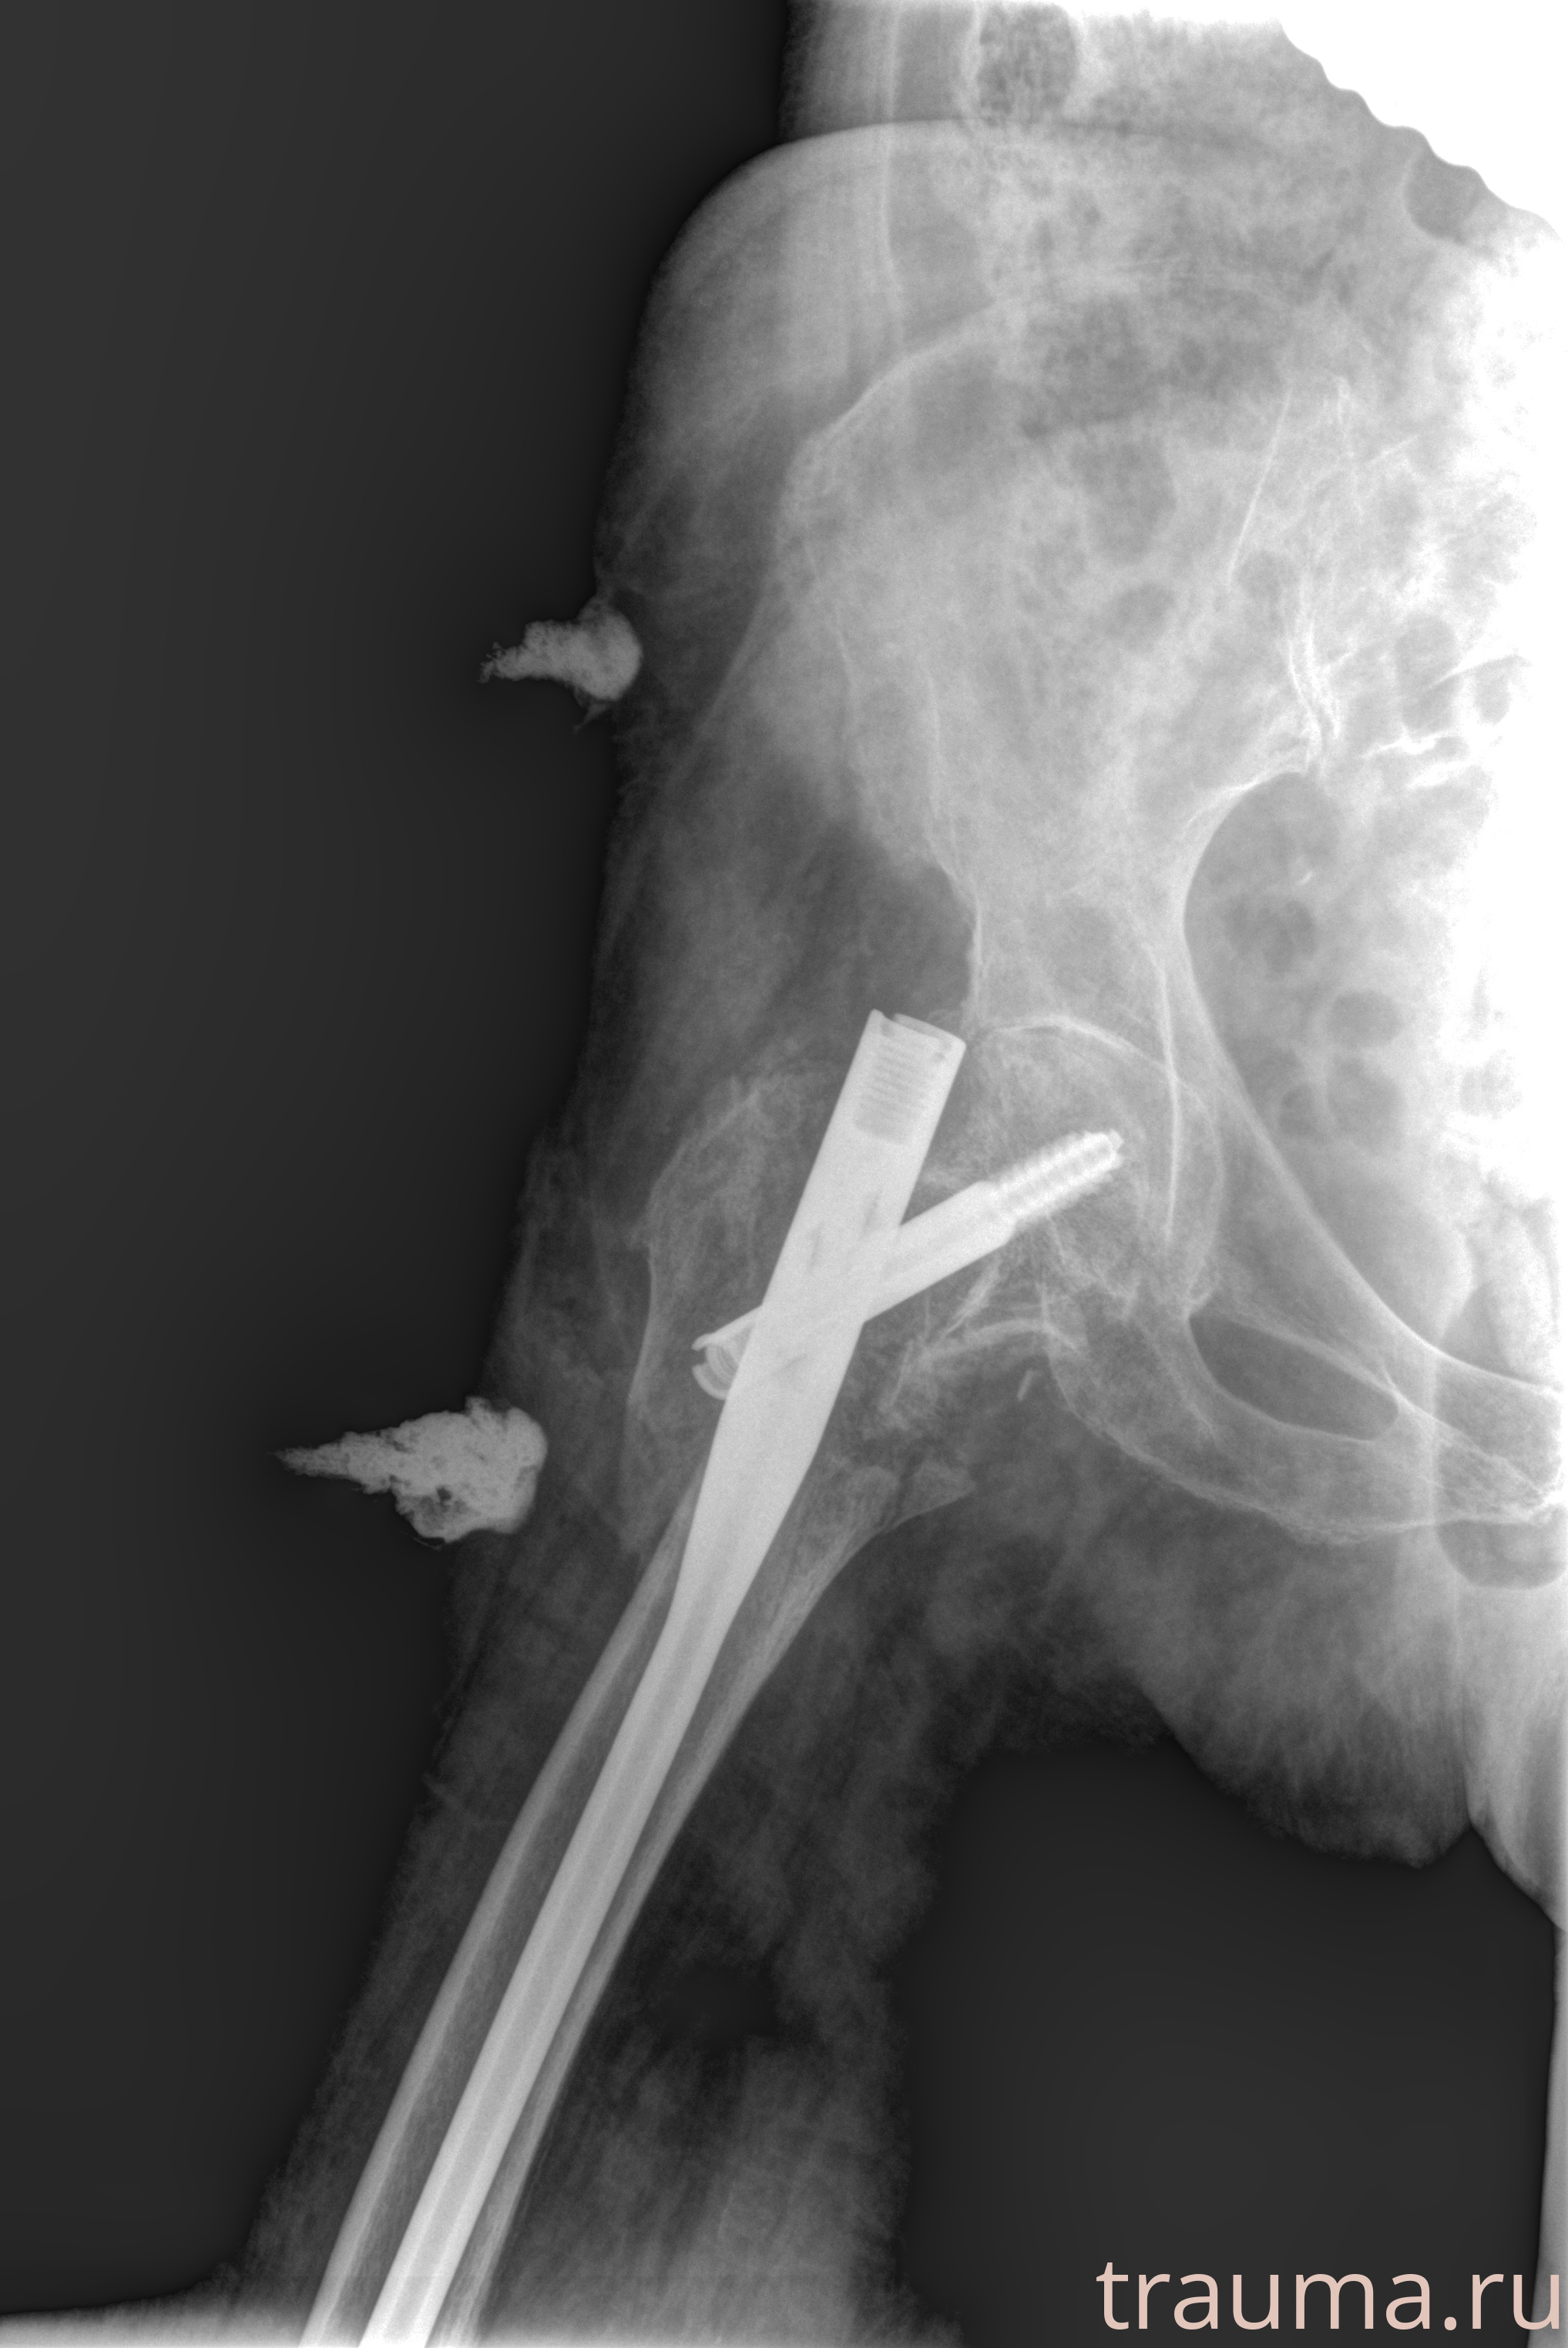

Рентгенограммы